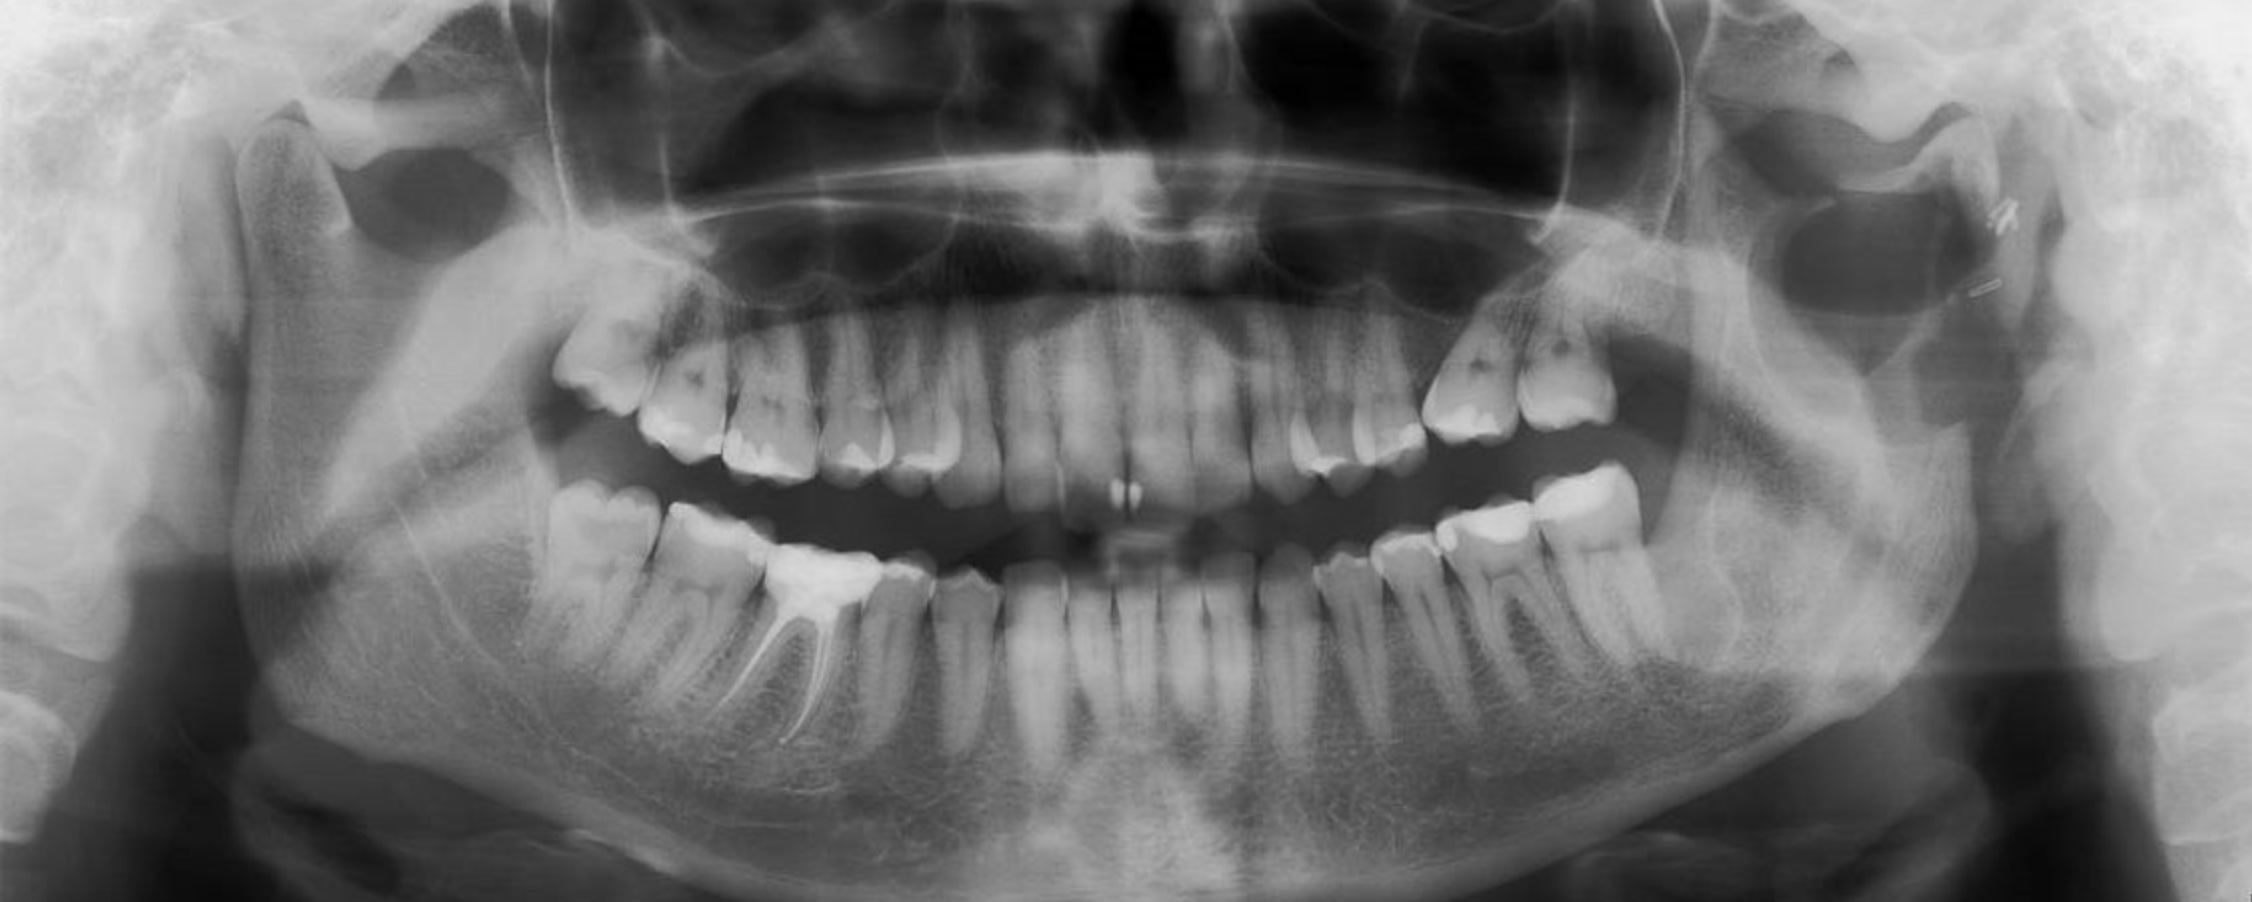

Cyst can often grow slowly within the bone, undetected. They are not uncommonly discovered as incidental findings on radiographs taken for other reasons. If your dentist uncovers a cyst as part of a routine investigation, they are welcome to refer you to me for rapid diagnosis and definitive management.

I will arrange for plain film radiographs and cross-sectional (3D) images of the cyst (such as a cone beam computed tomography scan or CBCT for short) to ensure that we carefully plan treatment together, laying the groundwork for the optimum chances of success and minimising the potential for damage to adjacent vital structures. These can include the maxillary sinuses and nerves that supply sensation to the lower lip, chin and/or tongue (the inferior alveolar and lingual nerves respectively).